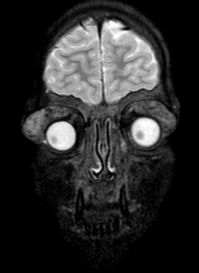

| Retinoblastoma[44] | Children | White reflex or strabismus. Most common intraocular tumor of childhood. | USG and MRI to distinguish RB from other causes of white reflex.

USG- evaluate calcification

CT- Radiation risk |

Retinoblastoma. a) Contrast-enhanced T1WI axial MRI image showing an enhancing right intraocular mass with no extraocular extension (orange arrow) b) T2WI axial MRI image showing hypointense signal (blue arrow) c) USG (B/A) showing intraocular mass lesion with specks of calcification corresponding to the spikes of A-scan. | |